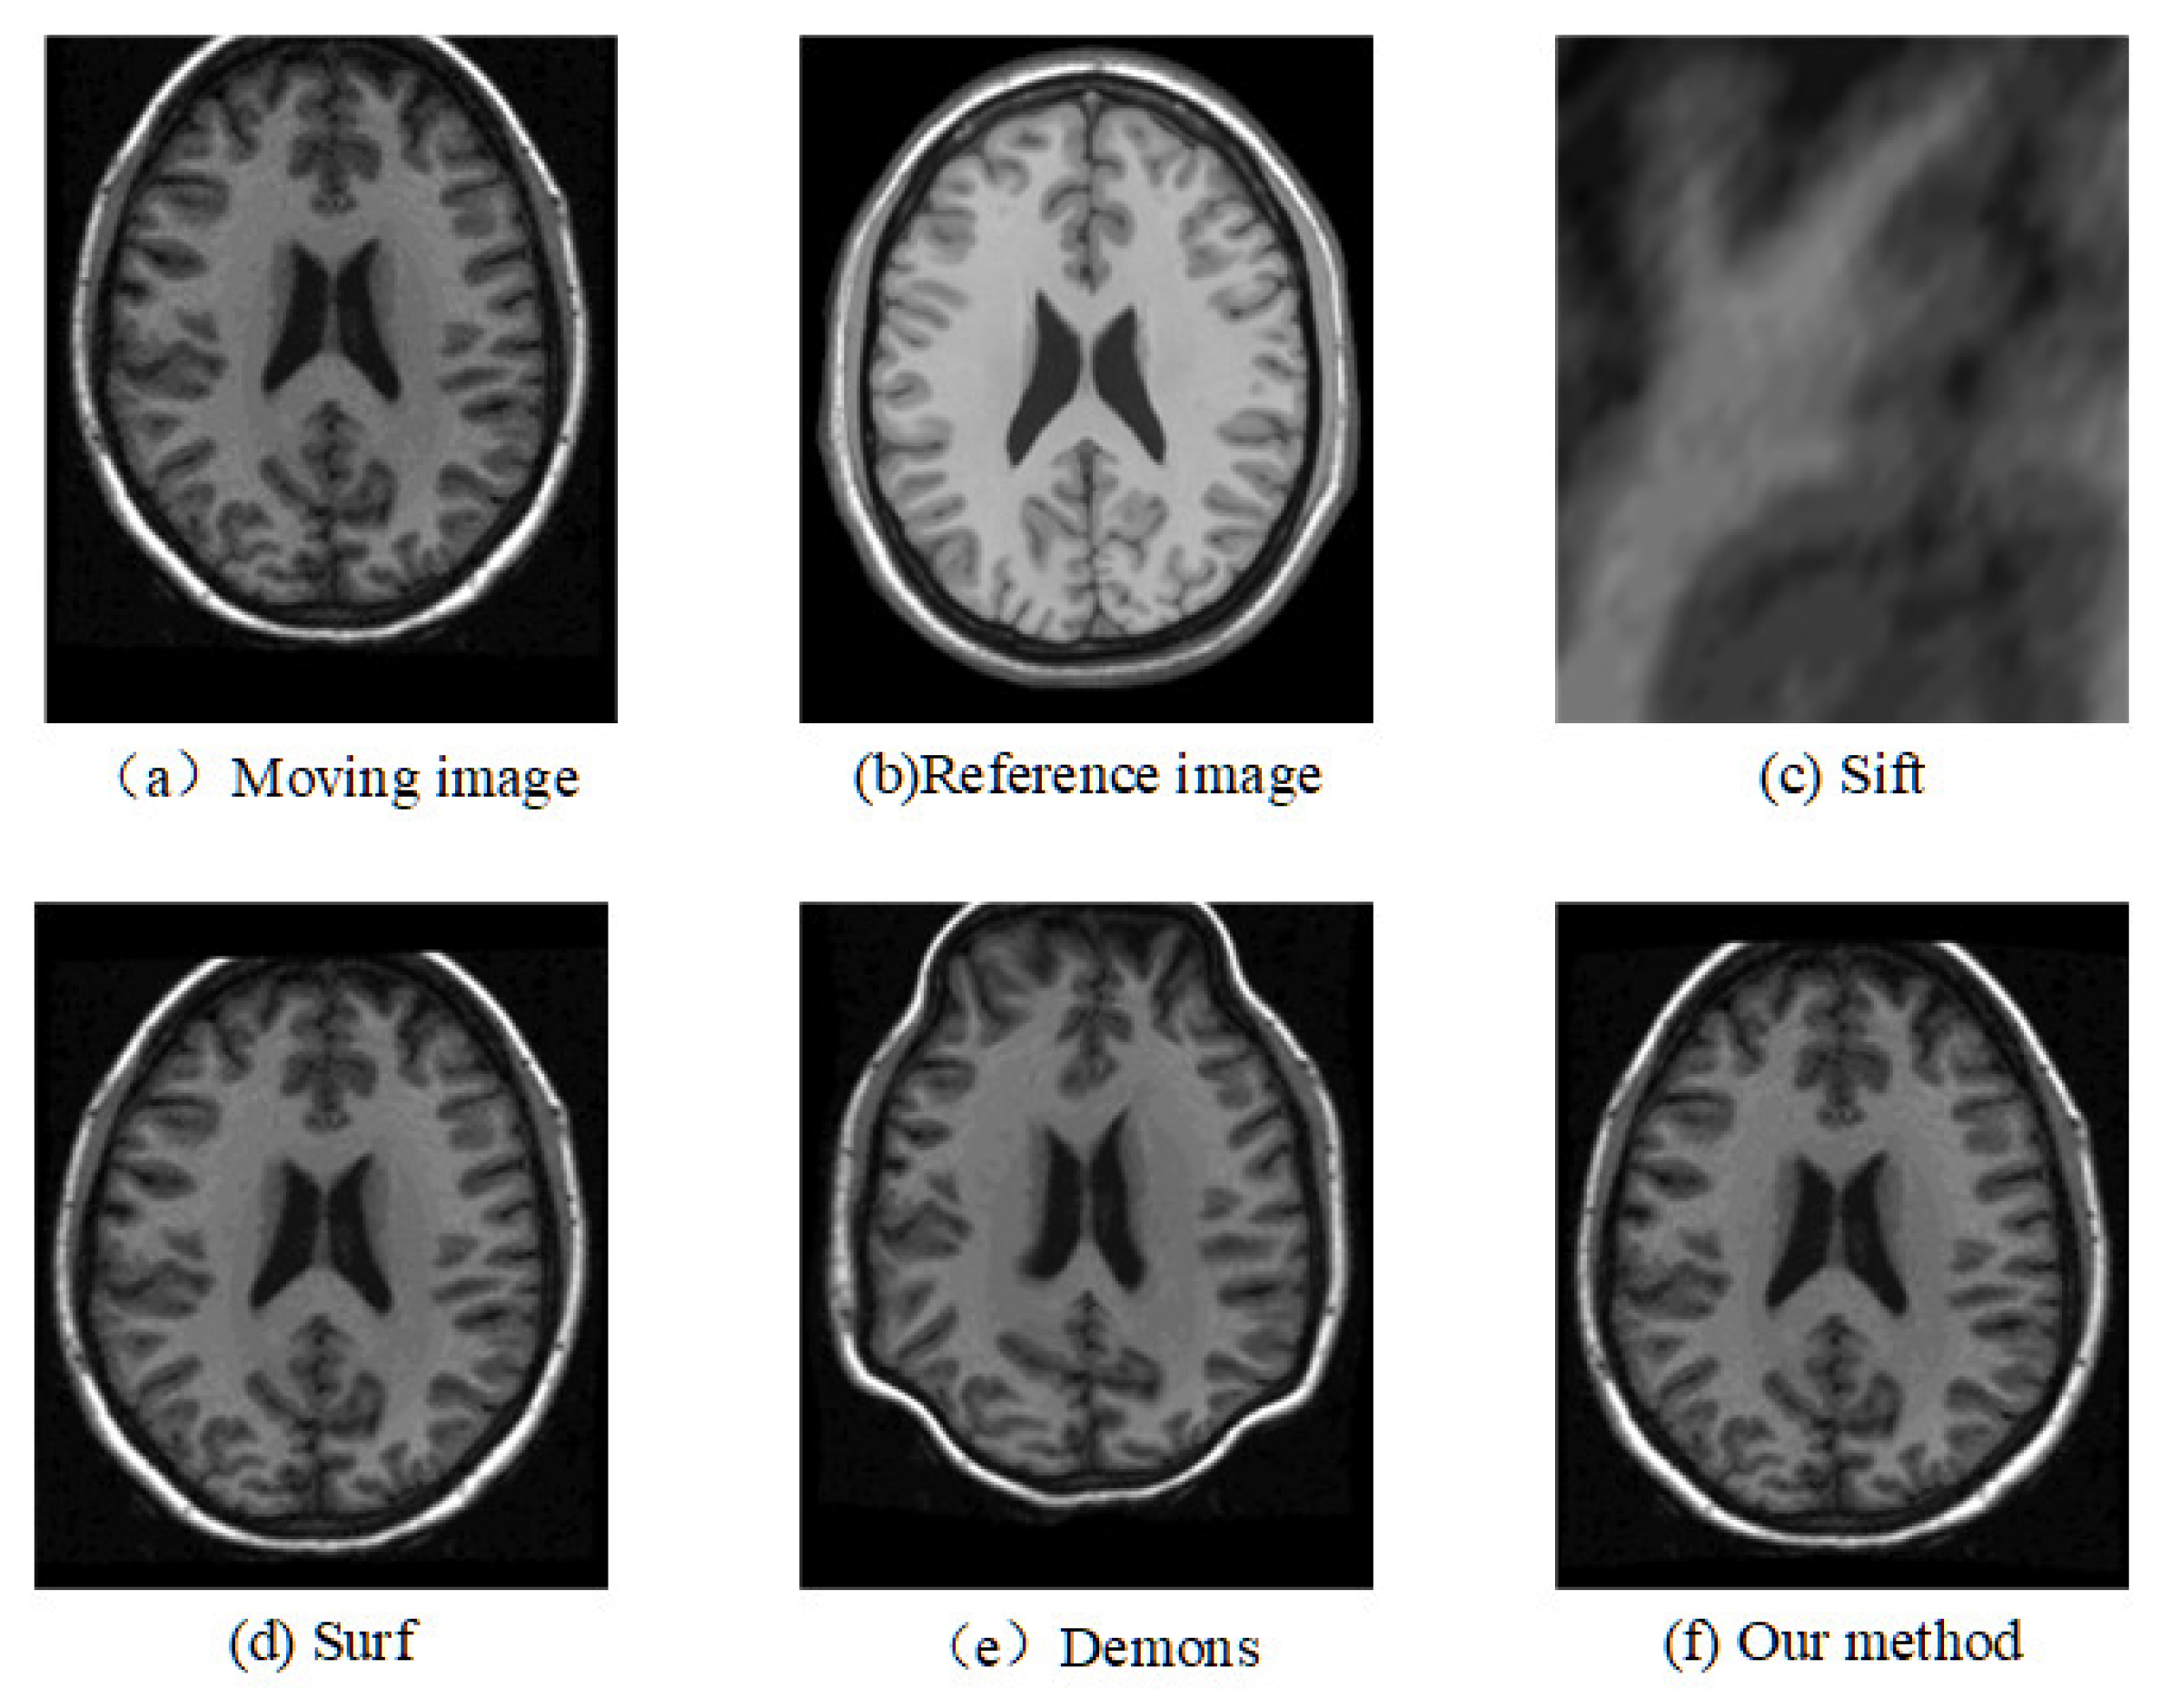

The registration results of the two datasets are shown in Table 1 and Table 2. Moreover, we randomly select two slices based on CUMC12, shown in Figure 6 and Figure 7, and those based on MGH10, shown in Figure 8 and Figure 9.

The corresponding relationship of spatial location can be seen in Figure 6 to Figure 9 between moving image and the reference image. These figures show lots of differences between the moving image and the reference image, including the significant shift of location, different size, the respective concavity and convexity of cerebral cortex, and different degree of smoothness. After registration, the results of our method are the closest to the reference image in multiple aspects, such as spatial location, image size, and brain contour. Surf is second-best, and close to the reference image for the spatial location and size. However, it represented the distortion in the contour of the cerebral cortex to some extent (as shown in Figure 6), and the skewing for some slices (as shown in Figure 8) after registration. The results of the Demons are totally different from the reference image in the spatial location, image size, and contour of the cerebral cortex. It also showed great distortion and deformation. Sift is the worst algorithm, and its current result did not show the brain shape.

Figure 8. Registration results of any one slice from any T1 image based on MGH10 dataset.